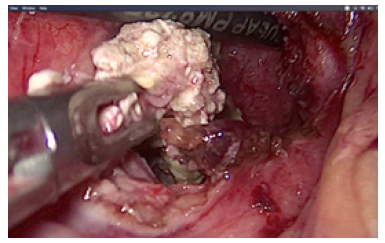

In ten cases we performed laparoscopic cholecystectomy with debridement of pancreatic necrosis. For 18 patients we explored the CBD by choledoscope and extraction of stones was done. The operation was finished with placement of T- tube drainage by laparoscopic approach. In 7 cases was accomplished percutaneous drainage of WOPN under US-control. For eight patients was applied a two-stage procedure. The first step was a placement of percutaneous biliary drainage under US-control and C-arm control. The second step was laparoscopic necrosectomy. A temporary loop ileostomy was performed in 5 cases because of bowel paralysis around the pancreas, paralytic ileus, abdominal distention and worsening of the patients’ condition. Debridement by laparoscopic access was accomplished by transgastric approach or gastrocolic access to enter the lesser sac. Applying a gentle blunt removal of necrotic tissue around pancreas, we take care of blood vessels around the pancreas, and we usually use a bipolar coagulation in case of bleeding from vital pancreatic tissues. We always take a sample from infected tissues for culture and subsequent precise antibiotic treatment (Figure 3).

Debridement of necrotic material was performed by forceps and with a laparoscopic irrigation/suction device with evacuation of infected debris (Figures 4-6).